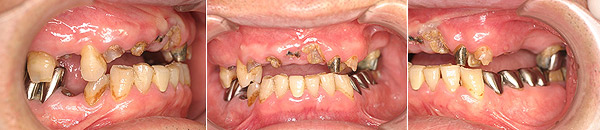

67歳男性の方です。初診時は、本人も上顎の歯すべて抜歯になり、総入れ歯を覚悟していたそうです。できる限り天然歯を温存し、治療は1年8ヶ月という長い期間かかりましたが、包括的な総合的治療により患者様に大変喜んで頂けるゴールを迎える事が出来、先日メンテナンスへ移行しました。

初診時